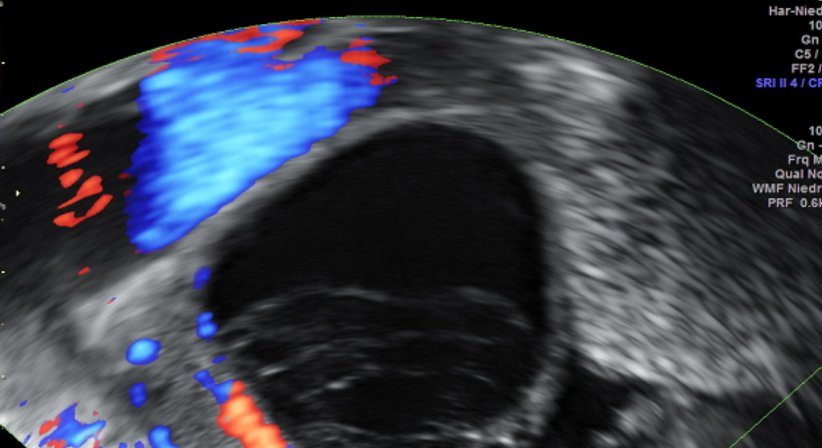

Zysten:

Zysten im Bereich der Eierstöcke sind grundsätzlich etwas sehr häufiges. Die meisten sind so genannte funktionelle Zysten, die durch Retention von Follikeln entstehen und üblicherweise nach einer oder zwei Menstruationsblutungen wieder verschwinden. Solche Zysten findet man nach der Menopause nicht mehr! Funktionelle Zysten sind eigentlich nicht weiter gefährlich, es sei denn, wenn sie an Größe zu stark zunehmen. Wenn dies geschieht, können sie durch die so genannte Stieldrehung (ähnlich wie bei einem geknickten Gartenschlauch) zu einem sehr akuten Bauchschmerz führen, der die sofortige Einlieferung in eine Krankenhaus erfordert.

Die Beurteilung von Eierstockzysten erfolgt üblicherweise durch ein geeignetes, hochwertiges Ultraschallgerät, da auch die Blutversorgung mittels Farbdoppler-Technik wichtig für die Differentialdiagnose ist.